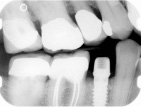

Radiographically, a dental implant looks like this:

Implant in bone Implant with crown attached

Here is an example of a single dental implant, where there are other missing teeth.